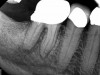

A body of research has emerged in recent years on the management of severe dental pain, exemplified by the diagnosis of an acute apical abscess where drainage cannot be achieved, symptomatic apical periodontitis, or irreversible pulpitis.11 An example of an acute apical abscess is depicted in Figure 1 and Figure 2. These conditions typically represent the most severe discomfort experienced by patients, and consequently, they serve as an excellent model for pain management. Treatment strategies for these issues and other painful conditions should include both definitive treatments for the diagnosed condition as well as adjunctive pharmacologic management.

(1.) A 74-year-old male presented with an acute apical abscess associated with tooth No. 30. The pre-operative periapical x-ray revealed evidence of apical pathology.

Figure 1

(2.) The infection was managed with oral antibiotics, root canal therapy, and a combination of ibuprofen and acetaminophen to manage the preoperative and postoperative discomfort.

Figure 2